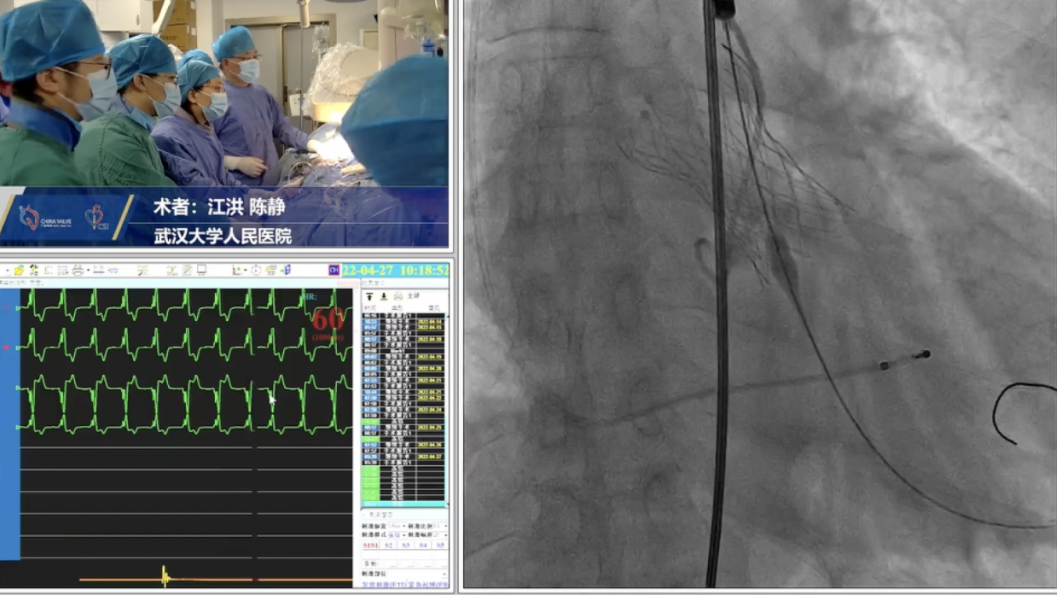

手术过程:

主动脉根部造影

球囊预扩

释放工作位评估

术后造影评估

跨瓣压差由术前38mmHg降低到5mmHg。

人工瓣膜精准定位